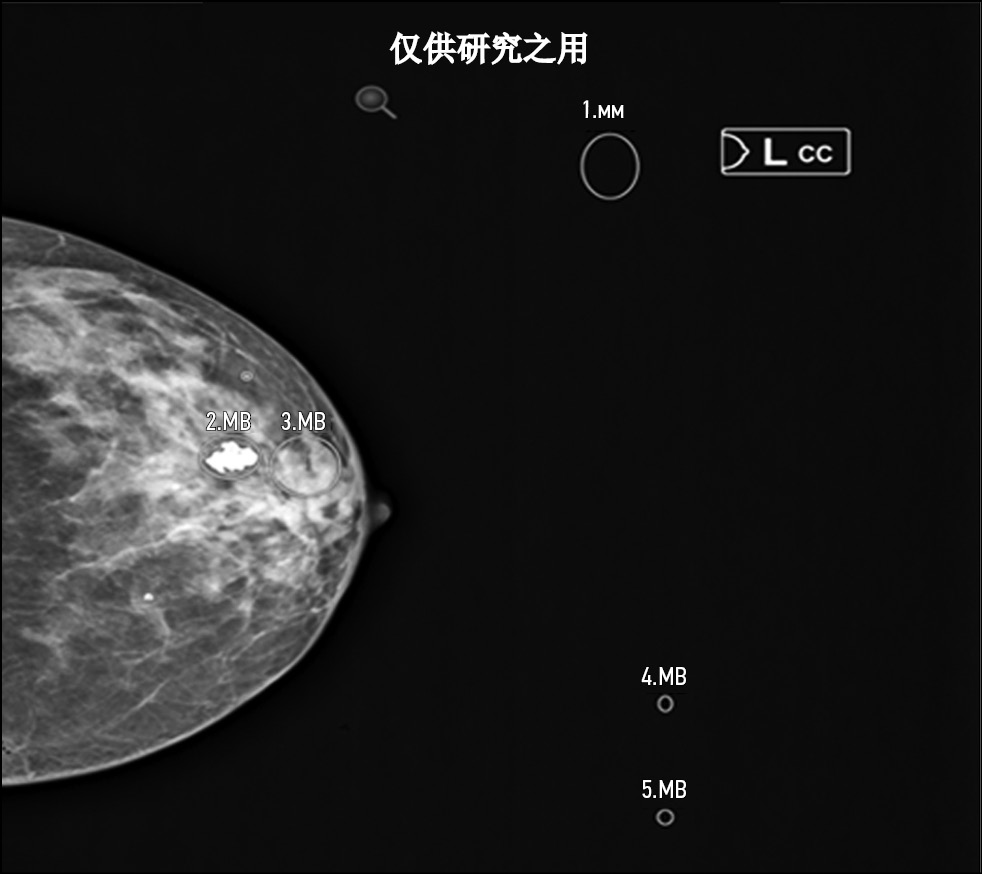

Figures 3, 4, 5, and 6 show examples of technological errors in AI-based software.

Fig. 3. Defect: not all necessary images have been evaluated. Modality: mammography.

Fig. 4. Defect: off-target markings; Modality: mammography.